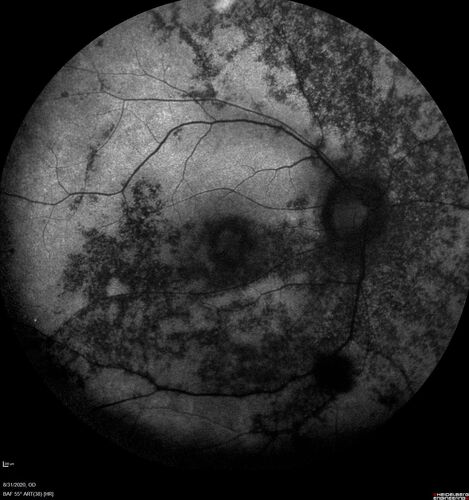

hydroxychloroquine (Plaquenil) Toxicity - Taiwanese - 3 years post stopping

59 year old female on 400 mg plaquenil for 22 years. 3 years ago, when stopping plaquenil, VA 20/50 both eyes.  Plaquenil was stopped.  The vision in the left eye continued to deteriorate to 3/200.  5'2" 127 lb (6.6 mg/kg body weight) -- Vision in these images is 20/80 OD, 5/200 OS - Vision loss now seems stable.